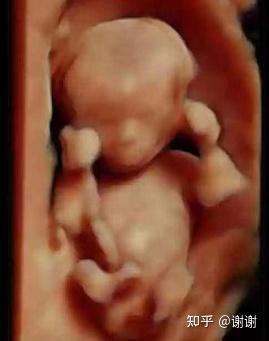

20周的胎儿有多大

怀孕20周胎宝宝图片

怀孕20周胎儿大小图片

怀孕20周胎儿图片

怀孕20周胎儿真实图片

怀孕20周胎儿高清图片